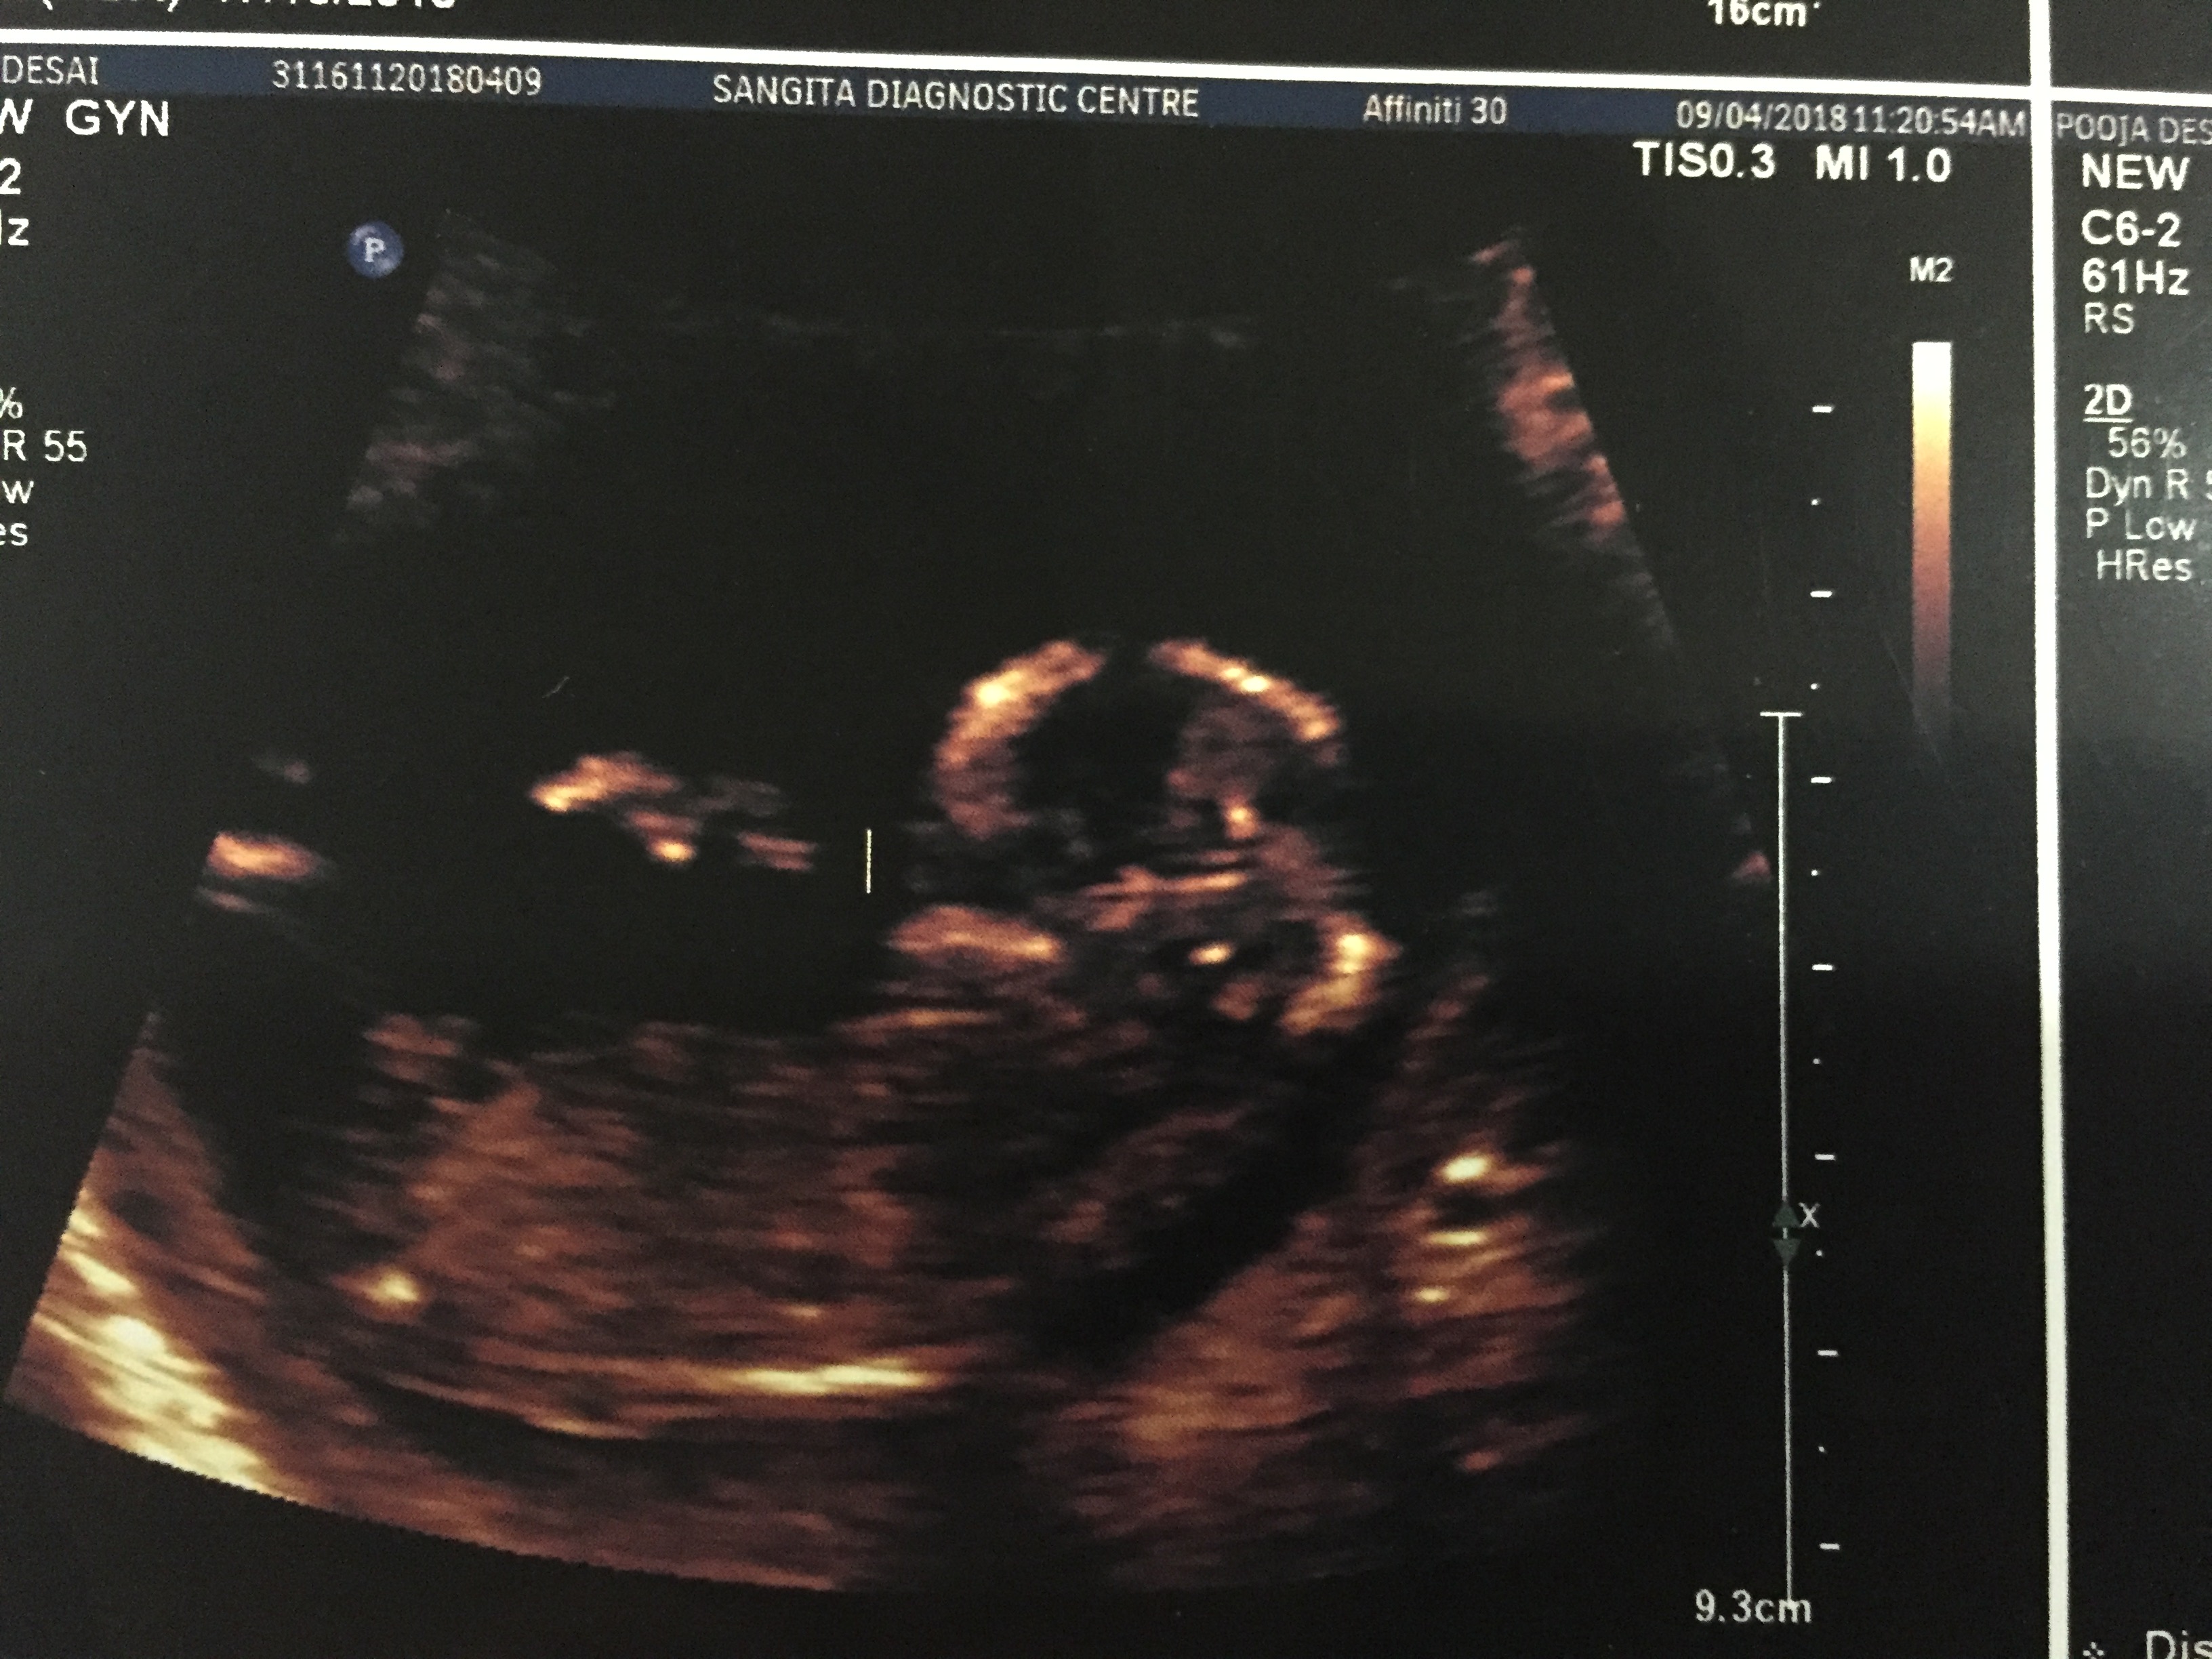

Attachment 39498Attachment 39499Attachment 39500Attachment 39501Attachment 39502

Guessing boy